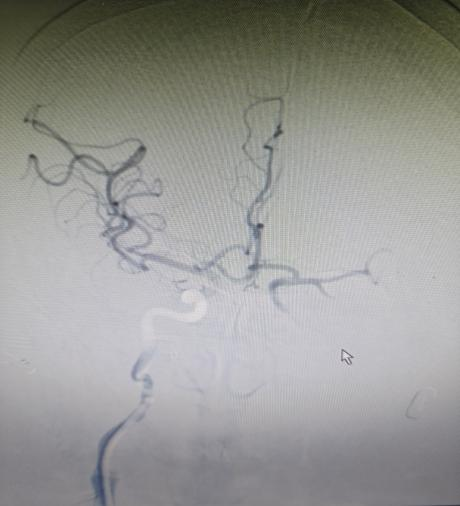

手术室内,神经内科张奕主任凭借丰富经验和精湛技术,在数字减影血管造影机引导下,经毫米级微创通道,将取栓器械精准送达闭塞血管核心部位。经不到1小时操作,成功完整取出堵塞血管的栓子,闭塞血管再通,脑部血供恢复。术后复查头颅 CT显示低灌注区脑组织全部存活。